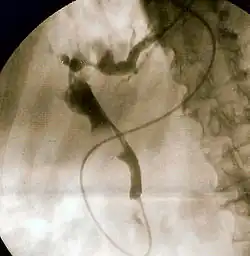

Fluoroscopic image of common bile duct

Hepatology is the branch of medicine that incorporates the study of liver, gallbladder, biliary tree, and pancreas as well as management of their disorders. Although traditionally considered a sub-specialty of gastroenterology, rapid expansion has led in some countries to doctors specializing solely on this area, who are called hepatologists.